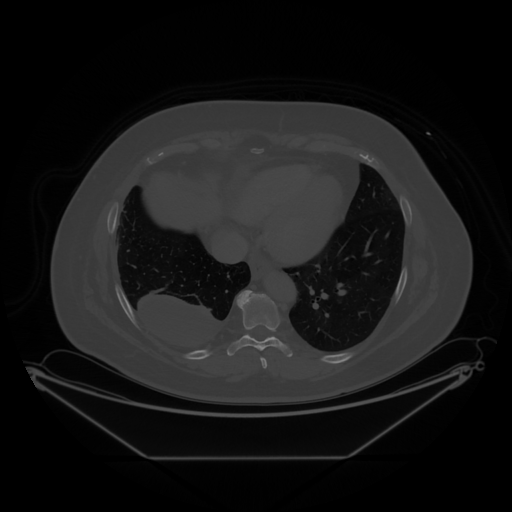

Original NATIVE CT scan (input)

Full window (WL 1023.5, WW 4095 β†’ Low βˆ’1024, High +3071)

Lung window (WL -600, WW 1500 β†’ Low βˆ’1350, High +150)

Mediastinum window (WL 40, WW 400 β†’ Low βˆ’160, High +240)